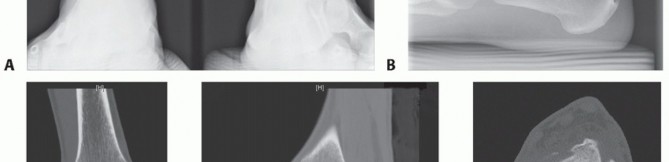

Anterior ankle arthrotomy (TECH FIG 1A)

Open the posterior tibial tendon sheath-flexor retinaculum, directly on the posterior margin of the tibia and medial malleolus (TECH FIG 1B). Protect the posterior tibial tendon: It rests in a groove immediately posterior to the tibia and is at great risk with a medial malleolar osteotomy.

- TECH FIG 1 • A. Medial incision and anterior ankle arthrotomy. B. Opening of the posterior tibial tendon sheath. C. Predrilling of medial malleolus. Kirschner wire for trajectory of medial malleolar osteotomy has already been inserted and its position confirmed with fluoroscopy. D. Fluoroscopic image demonstrating Kirschner wire being used as a guide to direct the saw. E. The periosteum is scored perpendicular to the tibial shaft, at the level of the osteotomy. F. Medial malleolar osteotomy. Care must be taken to protect the posterior tibial tendon. (continued)

- TECH FIG 2 • A,B. Identifying the extent of the talar shoulder lesion. (continued)